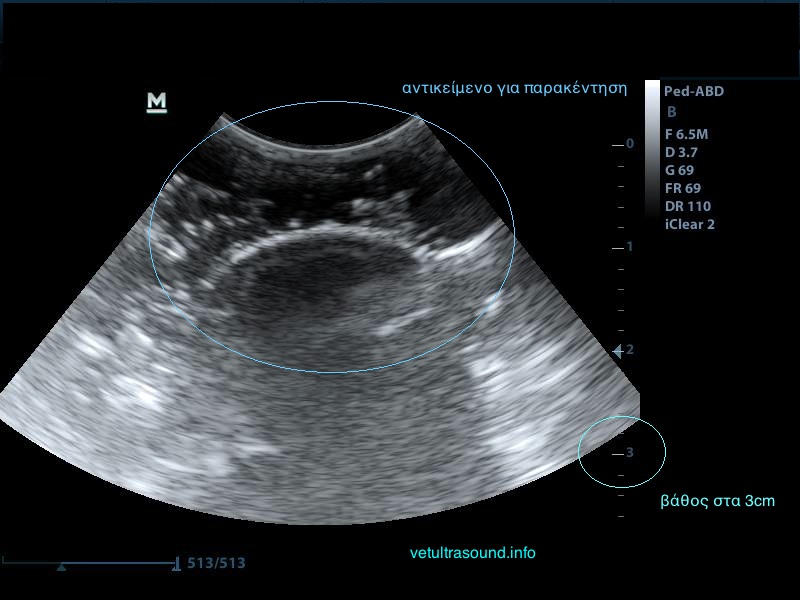

2) Το βάθος (depth), δηλαδή το να φέρουμε στην οθόνη του υπερήχου όσο το δυνατόν πιο κοντά το αντικείμενό μας, ώστε να καλύπτει σχεδόν τα 2/3 της οθόνης μας.

Μειώνουμε το βάθος ώστε να φέρουμε κοντά μας το αντικείμενο.